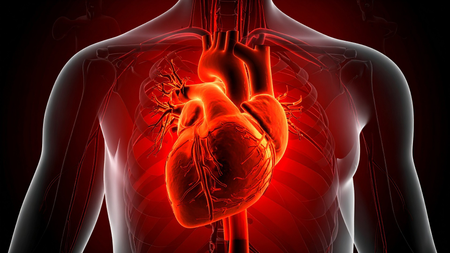

नई दिल्ली, 13 अक्टूबर (आईएएनएस)। दुनियाभर में हो रही कुल मौतों और दिव्यांगता के करीब दी तिहाई मामलों की वजह हृदय रोग, स्ट्रोक और मधुमेह जैसे गैर-संचारी रोग है। यह चौंकाने वाला अध्ययन सोमवार को ‘द लैंसेट’ पत्रिका में प्रकाशित हुआ।

इस अध्ययन के अनुसार हृदय रोग, स्ट्रोक और मधुमेह जैसे गैर-संचारी रोग (एनसीडी) दुनियाभर में मृत्यु दर और दिव्यांगता के प्रमुख कारण हैं।

इस्केमिक हृदय रोग (दिल का दौरा), स्ट्रोक और मधुमेह को भारत समेत दुनियाभर में मृत्यु दर और रुग्णता के प्रमुख कारणों के रूप में पहचाना गया है। इसके बाद क्रॉनिक ऑब्सट्रक्टिव पल्मोनरी डिजीज (सीओपीडी), निचले श्वसन संक्रमण और नवजात विकार आते हैं।

1990 में जहां डायरिया संबंधी बीमारियां मृत्यु का प्रमुख कारण थीं। अधिक उम्र की वजह से प्रति लाख जनसंख्या में से 300.53 लोगों की मौत होती थी। 2023 में इस्केमिक हृदय रोग के कारण सबसे अधिक मौतें हुईं, जिसकी आयु-मानकीकृत मृत्यु दर (एएसएमआर) 127.82 प्रति लाख जनसंख्या थी।